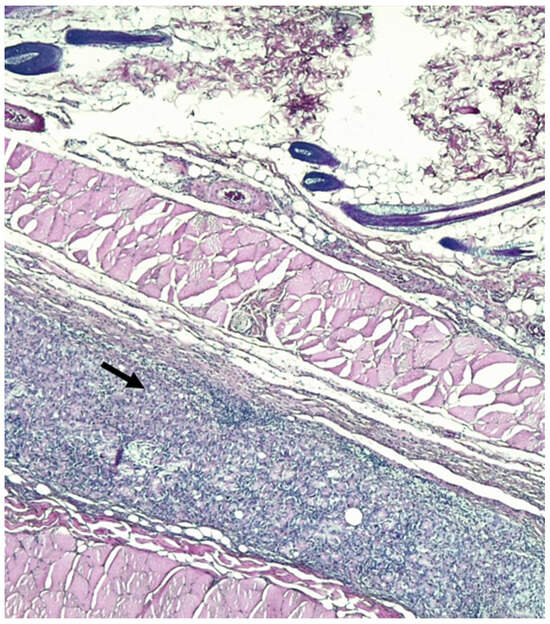

2.3. Histological Evaluation and Immunohistochemical Analysis

| Cells layers at margins of the granulomas | 3 (2–3) | 2,5 (2–3) | 0.59 |

| Inflammatory reaction in the host tissue | 3 (2–4) | 2 (2–3) | 0.23 |

| Inflammatory response on the mesh surface | 3 (2–4) | 3 (2–4) | 0.63 |

| Tissue maturation | 3 (2–4) | 2 (1–3) | 0.28 |